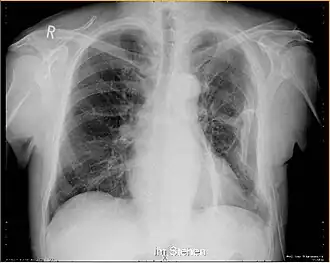

Die Diagnose einer Rippenfraktur ist oft schon vom Tastbefund her möglich. Der starke Schmerz und ein knirschendes Geräusch (Krepitation) bei Bewegung sind wegweisend. Bei größerer Verschiebung der Rippen lässt sich die Fraktur in Röntgenaufnahmen des Thorax in mehreren Ebenen nachweisen. Auch die Bildgebung mittels CT kann eine Rippenfraktur aufzeigen. Brüche ohne Dislokation (Verschiebungen der Bruchränder) wurden früher oft als Prellung fehlgedeutet, sie sind häufig nur mit dem Ultraschall darstellbar. Zum Ausschluss weiterer Verletzungen kann ein Ultraschall des Bauchraumes, der Pleura und des Herzens nötig sein.

Die Behandlung erfolgt in der Regel konservativ. Der Patient erhält eine Aufklärung über die Erkrankung und wird auf einen etwa zwei- bis dreiwöchigen Krankheitsverlauf aufmerksam gemacht. Die Schmerzen können mit Schmerzmitteln behandelt werden. Eine Ruhigstellung durch einen Gips oder eine Verplattung sind nicht üblich. Bei Komplikationen wie starker Luftnot muss der Patient erneut geröntgt werden, um ein Kollabieren der Lunge (Pneumothorax) oder einen Bluterguss (Hämatothorax) auszuschließen.